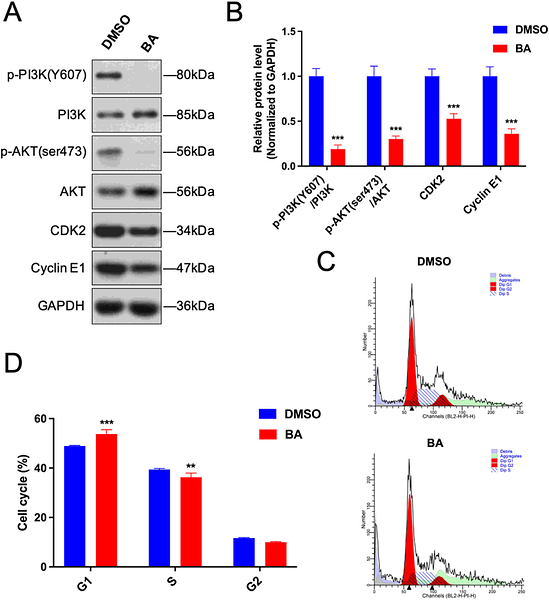

Betulinic Acid Inhibits Glioma Progression by Inducing Ferroptosis Through the PI3K/Akt and NRF2/HO-1 Pathways

Author: Jinxiang Huang, Qixuan Li, Hongxiang Wang, Shuai Zhang, Xiaorong Zhou, Fang Huang, Juxiang Chen, Luning Xu, Dezhi Kang

PMID: 39965807

期刊: Journal Of Gene Medicine

应用: WB

反应种属: Human

发表时间: 2025 Feb